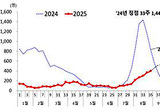

코로나19 이달까지 유행 지속 예상

- 2025-09-05 17:14

- 황재연 기자